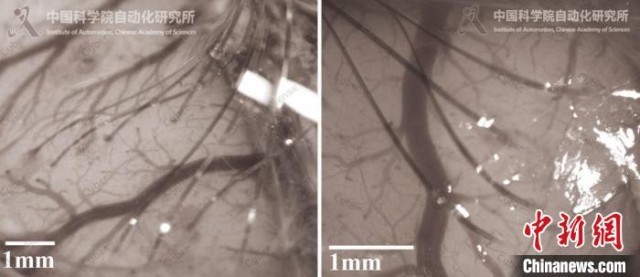

动物大脑皮层多电极植入效果。中国科学院自动化所 供图